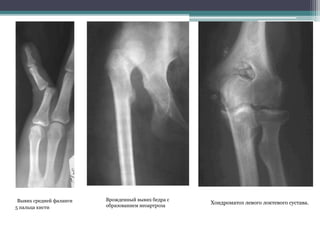

Вывих средней фаланги

5 пальца кисти

Врожденный вывих бедра с

образованием неоартроза

Хондроматоз левого локтевого сустава.